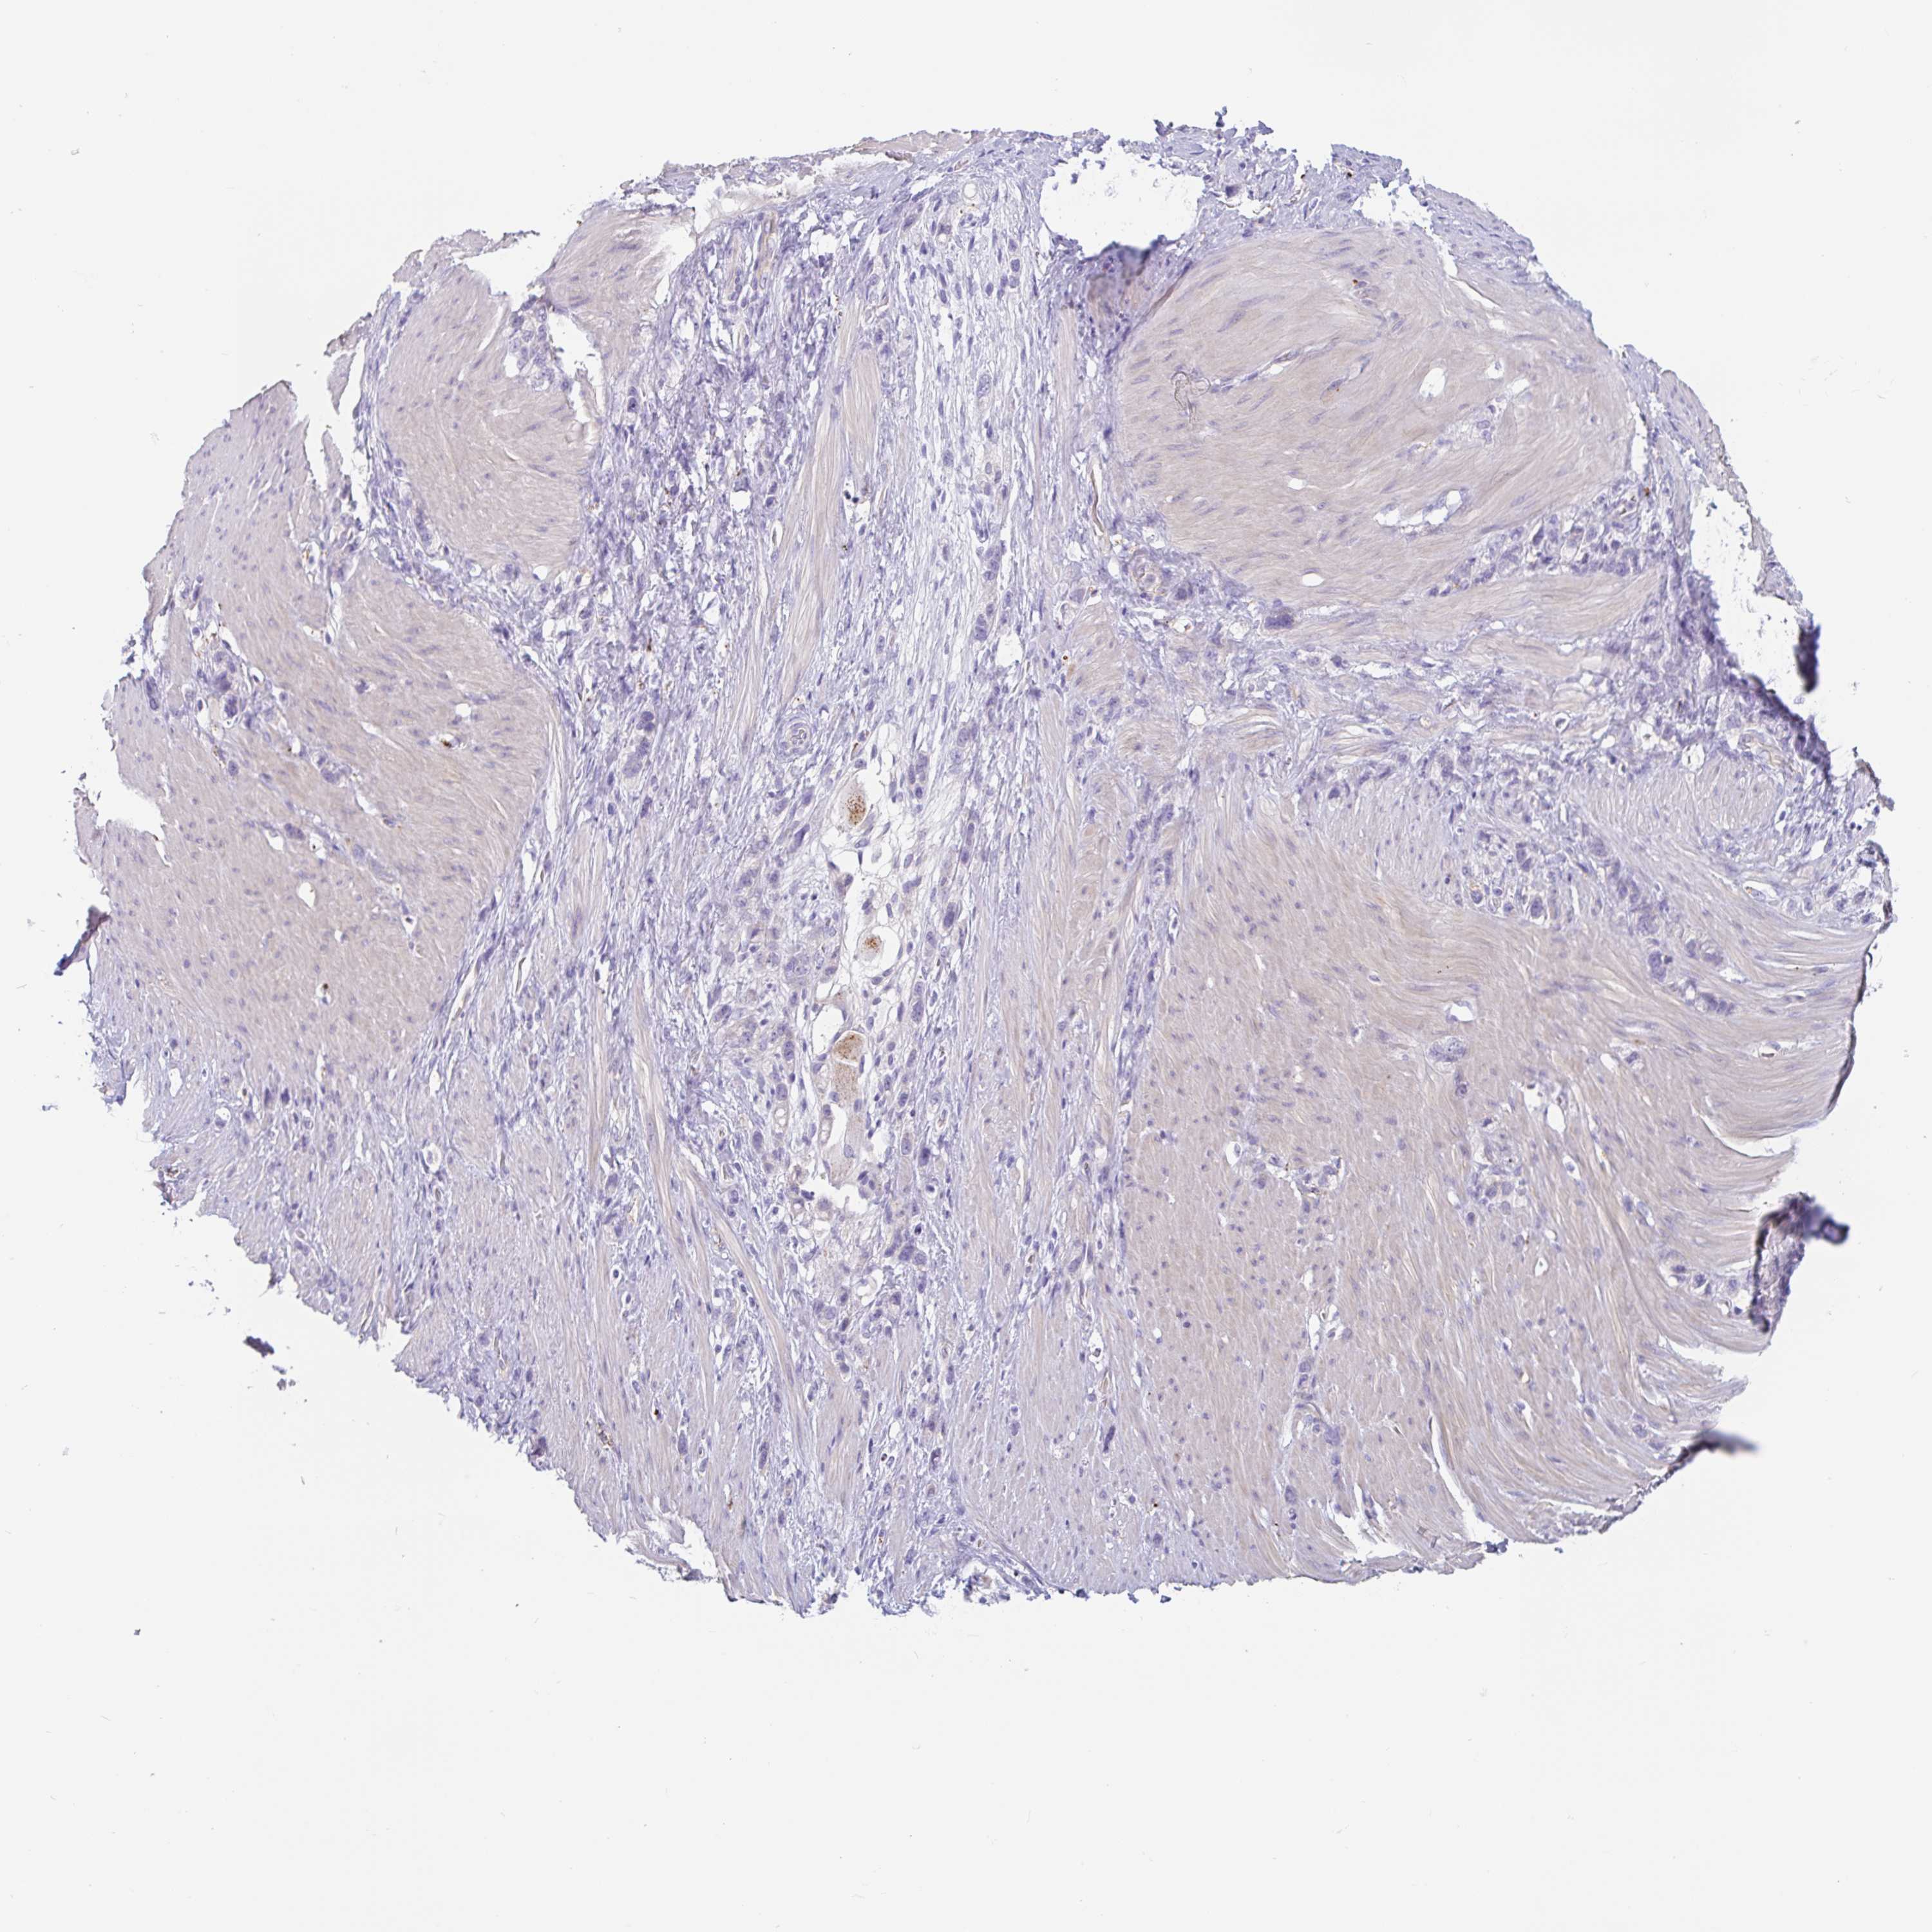

STOMACH CANCER - Protein expressioni

A mouse-over function shows sample information and annotation data. Click on an image to view it in a full screen mode. Samples can be filtered based on level of antibody staining by selecting one or several of the following categories: high, medium, low and not detected. The assay and annotation is described here.

Note that samples used for immunohistochemistry by the Human Protein Atlas do not correspond to samples in the TCGA dataset.

Antibody stainingi

Antibody staining in the annotated cell types in the current human tissue is reported as not detected, low, medium, or high, based on conventional immunohistochemistry profiling in selected tissues. This score is based on the combination of the staining intensity and fraction of stained cells.

Each image is clickable and will lead to virtual microscopy that enables deeper exploration of all samples and also displays staining intensity scores, fraction scores and subcellular localization as well as patient and tissue information for each sample.

Antibody HPA051671

Antibody HPA053556

Staining

High

Medium

Low

Not detected

Adenocarcinoma, NOS